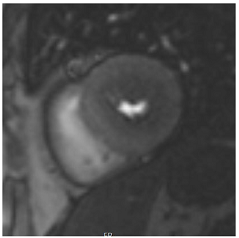

Table 3 summarises a suggested CMR scan protocol for the diagnosis of presumed HHD and differential diagnosis of patients with a “thickened left ventricle”.

Table 3.

The cardiovascular magnetic resonance protocol used for assessment of hypertensive patients. The described protocol can be acquired within 45–50 min. Images are examples from patients with hypertensive heart disease.

To avoid the low but important risks of endomyocardial biopsy, which can have an overall complication rate of up to 6% [2], myocardial fibrosis can be assessed non-invasively using CMR: LGE is suitable for detecting irreversible replacement fibrosis and myocardial scarring and T1/ECV mapping for detection of potentially reversible (reactive) interstitial and more diffuse fibrosis (not detectable by LGE) (Figure 2).

10. Tissue Characterisation with T1 and Extracellular Volume (ECV) Mapping

LGE allows the detection of focal alterations in the myocardium, but diffuse fibrosis may go undetected on LGE imaging. Tissue characterisation with parametric mapping methods such as T1 and ECV mapping has the potential to detect and quantify both focal and diffuse alterations in the myocardial structure. Furthermore, changes in the myocardium over time may be assessed longitudinally [40]. Estimation of myocardial ECV (interstitium and extracellular matrix) requires the measurement of myocardial and blood T1 before and after the administration of contrast agents, as well as the patient’s haematocrit. ECV can then be calculated using the formula:

Myocytes account for approximately one-third of all cells in normal myocardium. The remaining two-thirds of cells include endothelial and vascular smooth muscle cells and fibroblasts in interstitial/perivascular spaces [2] (Figure 2). Normal CMR ECV values vary between 25.3 and 3.5% [43]. Ideally, age- and sex-corrected normal values for ECV should be used [44]. Hypertension affects both the cellular and extracellular compartments of the myocardium. In addition to cardiomyocyte hypertrophy, in HHD, fibrous tissue (primarily type I fibrillar collagen) is deposited in the extracellular matrix over time and leads to increased tissue stiffness (i.e., diastolic dysfunction) [2]. ECV values are higher in hypertensive patients with LVH than in patients without LVH, and eccentric forms of hypertrophy seem to have the most fibrosis and highest ECV values, together with more pronounced systolic impairment and are associated with a poor cardiovascular prognosis (Figure 1) [2,6]. CMR-derived T1 mapping and strain analysis seem to be related, but an adequate comparison of the performance of these parameters is often limited due to the lack of harmonization of measurement methods [35]. Furthermore, ECV values seem to correlate with many blood biomarkers associated with (i) systemic inflammation; (ii) metabolism; (iii) fibrosis; (iv) chemotaxis; and (v) platelet activation [6]. This may suggest that an increase in ECV in hypertensive patients is a (non-specific) imaging biomarker of inflammation, tissue remodelling, atherogenesis, or metabolic disorder in patients with HHD [6]. Given the clinical consequences of myocardial fibrosis in HHD and considering the potential for recovery of fibrosis with appropriate treatment, the need for an accurate diagnosis of myocardial fibrosis is apparent.